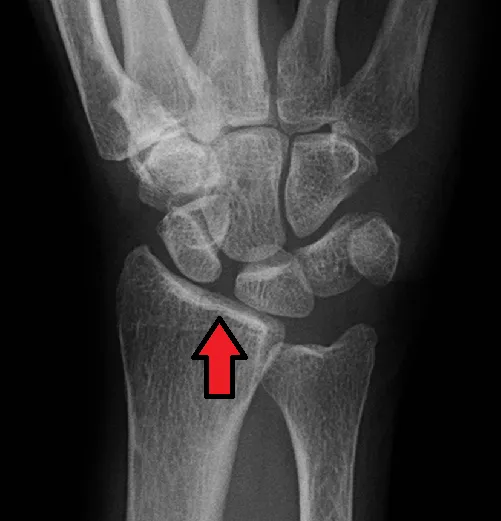

- Röntgenfoto (RX): Eerst wordt een röntgenfoto gemaakt. Bij een volledige scapholunaire scheur kan op de foto een vergrote ruimte te zien zijn tussen het scaphoid en lunatum (het zogenaamde Terry Thomas sign). Soms is dit alleen zichtbaar op specifieke opnamen, zoals een clenched fist view (röntgenfoto terwijl je een vuist maakt).